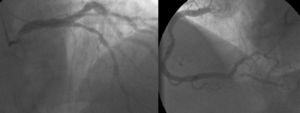

O doente teve alta ao 24.° dia de internamento, em classe NYHA II. No ecocardiograma transtorácico à data de alta apresentava compromisso moderado a grave da FSG (Figura 4), gradiente valvular aórtico médio de 31mmHg e área valvular de 1,06cm2. Programou-se cirurgia cardíaca, após cumprimento de um mês de dupla antiagregação plaquetar.